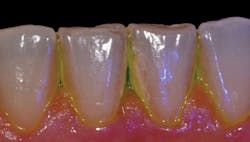

Figure 3: Plaque HD toothpaste discloses plaque left behind.

In an effort to improve daily plaque removal, Plaque HD toothpaste has incorporated a plant-based dye called Targetol. The dye adheres to plaque biofilm and leaves a brilliant teal color visible on surfaces with remaining plaque (see Figure 3). Patients could be instructed to use this at the beginning of a dental visit to see what they are leaving behind and where biofilm still remains. It is impossible to miss the brilliant teal color. A small-population clinical trial, recently published in the International Journal of Dentistry and Oral Science, reported a 51.3% reduction in visible plaque when brushing with Plaque HD compared to toothpastes without disclosing agents.2 If you haven't tried disclosing toothpaste yet, here's a warning: It can be a humbling experience the first time you brush with it.